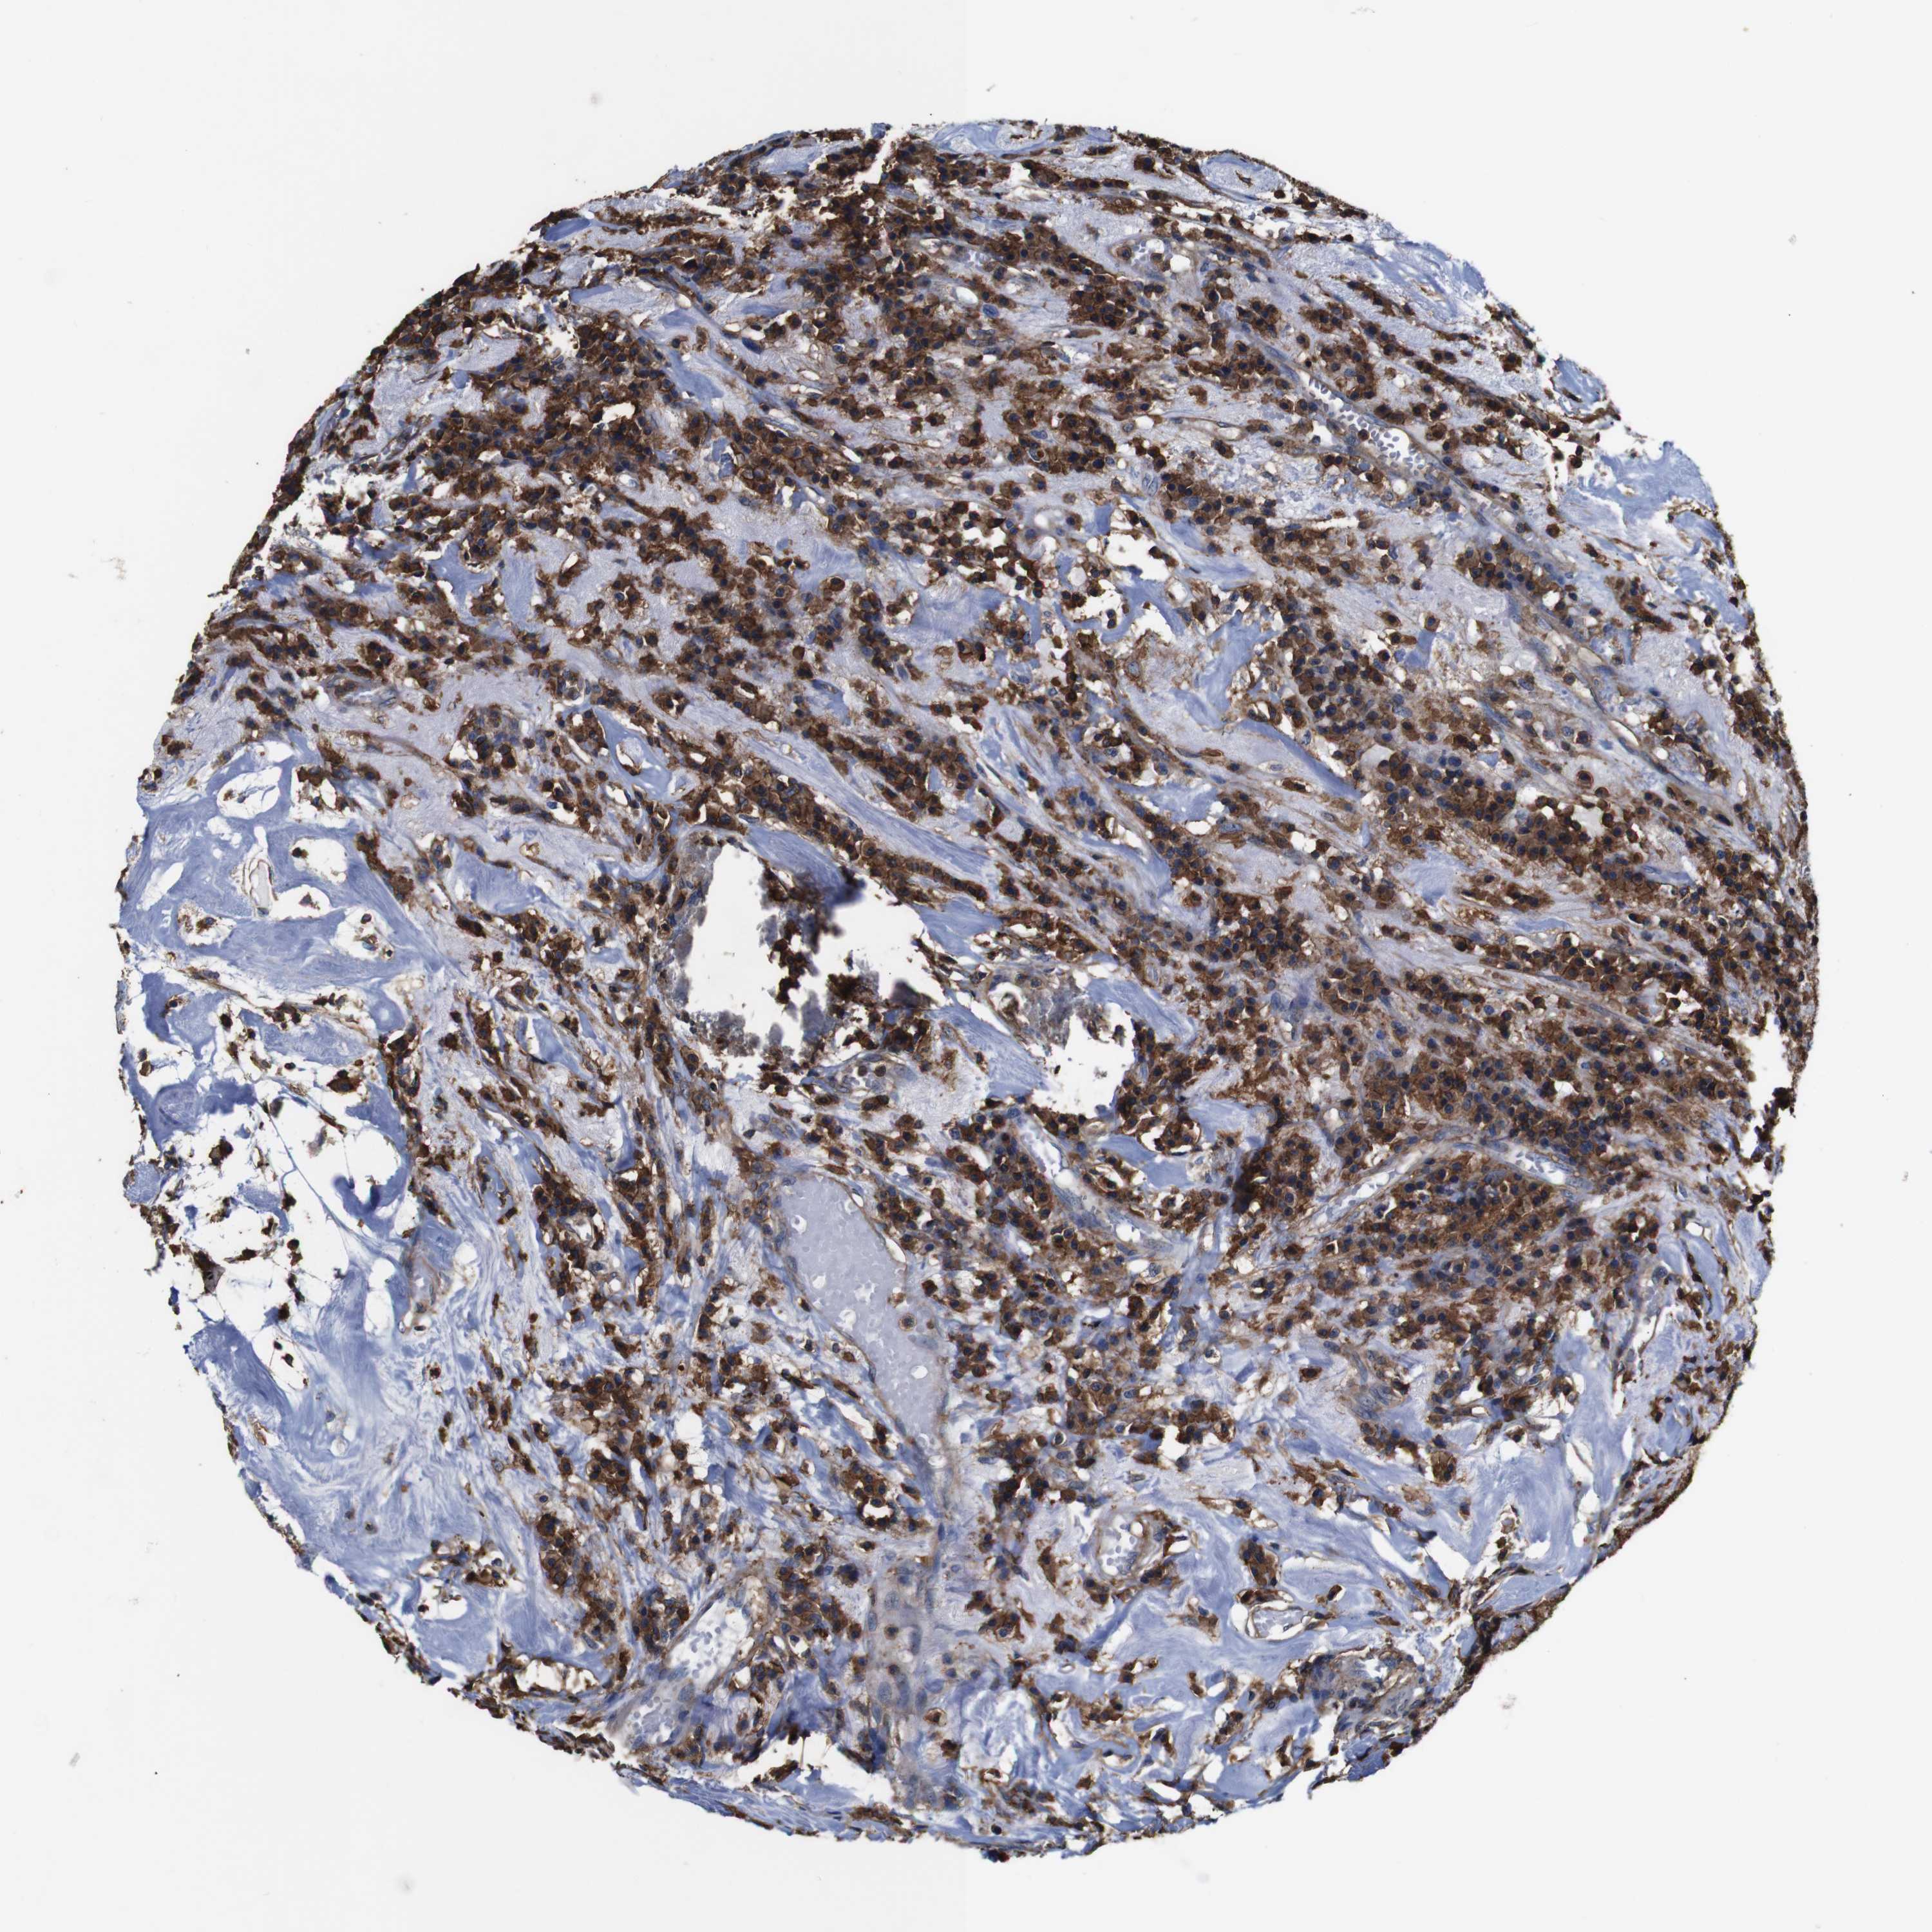

HEAD AND NECK CANCER - Protein expressioni

A mouse-over function shows sample information and annotation data. Click on an image to view it in a full screen mode. Samples can be filtered based on level of antibody staining by selecting one or several of the following categories: high, medium, low and not detected. The assay and annotation is described here.

Antibody stainingi

Antibody staining in the annotated cell types in the current human tissue is reported as not detected, low, medium, or high, based on conventional immunohistochemistry profiling in selected tissues. This score is based on the combination of the staining intensity and fraction of stained cells.

Each image is clickable and will lead to virtual microscopy that enables deeper exploration of all samples and also displays staining intensity scores, fraction scores and subcellular localization as well as patient and tissue information for each sample.

Antibody CAB009092

Staining

High

Medium

Low

Not detected

Intensity

Strong

Moderate

Weak

Negative

Quantity

>75%

75%-25%

<25%

None

Location

Nuclear

Cytoplasmic/membranous

Cytoplasmic/membranous,nuclear

Squamous cell carcinoma, NOS

Squamous cell carcinoma, metastatic, NOS

Adenocarcinoma, NOS